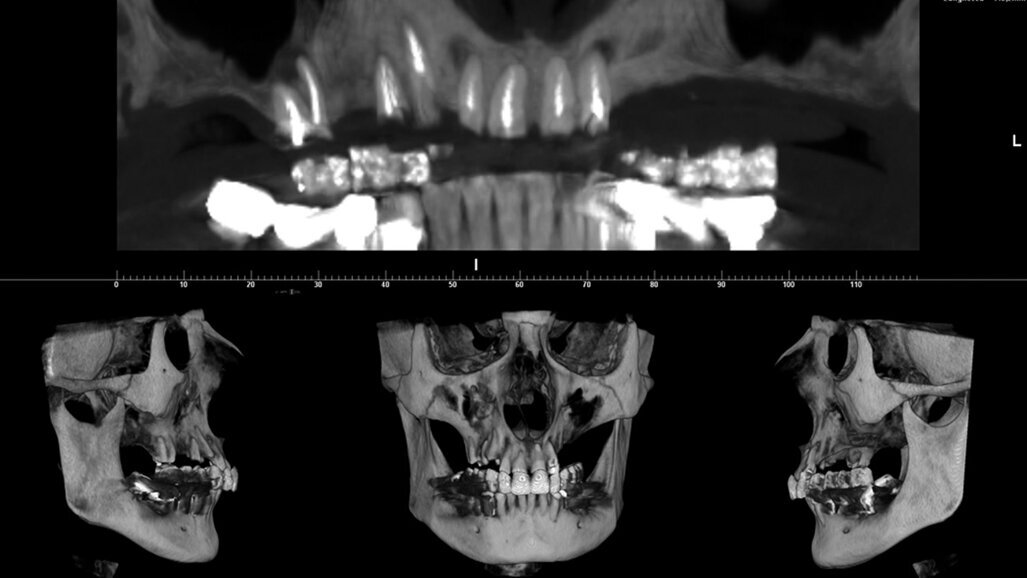

La paziente, di 54 anni, si è presentata al Centro Odontoiatrico Dentalnarco a Trezzano Sul Naviglio, Milano, Italia con tutti gli elementi residui del mascellare superiore compromessi (elementi 1.6, 1.4, 1.3, 1.2, 1,1 nel quadrante destro e 2.1 e 2.2 nel quadrante sinistro) (Fig. 1). A livello anamnestico, la paziente presentava un pregresso episodio di trombosi cerebrale ed era quindi in terapia anticoagulante con warfarin sodico (Coumadin, Bristol-Myers Squibb Srl, Roma, Italia); riguardo al valore INR (dall’inglese International Normalized Ratio), il range terapeutico impostato dai medici curanti era di 3. Avendo la paziente richiesto la massima riduzione possibile in termini di invasività dell’intervento, è stato dunque escluso in questa fase un intervento di grande rialzo di seno nel quadrante 2 e si è optato per un intervento di ridge preservation contestuale alle avulsioni. Per procedere alla corretta elaborazione del piano di trattamento, la paziente è stata sottoposta ad esame CBCT utilizzando un dispositivo ad alta risoluzione (Xmind TRIUM, ACTEON, Milano, Italia) con un FOV di 12 x 8 cm. Considerato il biotipo tissutale sottile della paziente, l’estensione dell’area crestale oggetto di trattamento e l’esiguo spessore della corticale vestibolare (Fig. 2), alla paziente è stato proposto un piano di trattamento che prevedeva l’avulsione di tutti gli elementi, l’innesto di un biomateriale a lento riassorbimento, il posizionamento di 5 impianti in un secondo tempo chirurgico e la riabilitazione definitiva attraverso una protesi fissa con chiavistelli liberamente rimovibile dal paziente. La paziente ha accettato il piano di trattamento e fornito il proprio consenso informato.

Fig. 1_CBCT e ricostruzione tridimensionale del massiccio facciale della paziente. I sette elementi ancora presenti nel mascellare superiore sono compromessi.